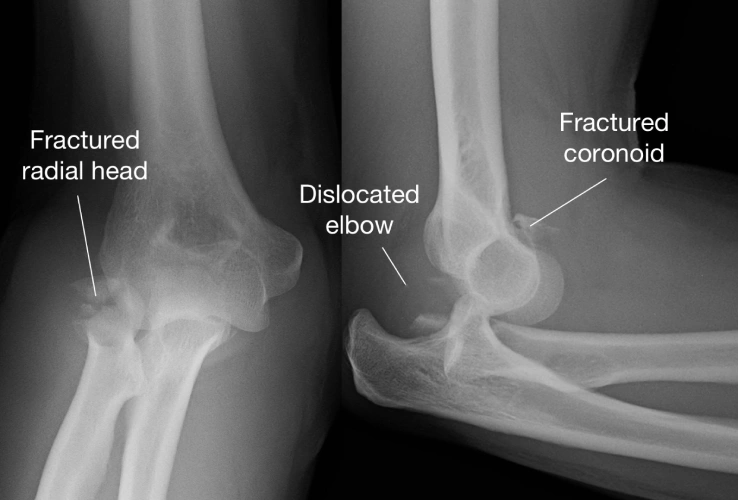

Types of Elbow Fractures1. Distal Humerus Fracture – break in the lower end of the upper arm bone.

3.Radial Head Fracture – break in the top of the radius near the elbow joint.

4.Coronoid Fracture – less common, involving a small part of the ulna that stabilizes the joint.

X-rays to confirm the type and severity of fracture